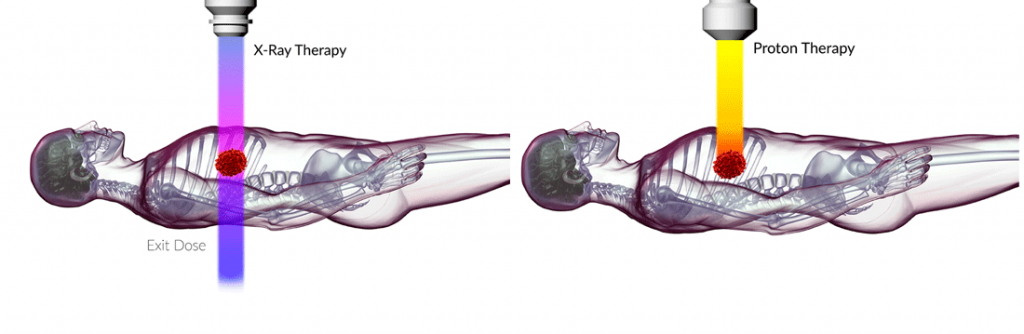

پروتوندرمانی (PBT) گونهای از درمان است که با استفاده از پروتونها، سرطان را مداوا میکند. پروتون ذرهای با بار مثبت است و دستگاهی به نام Synchrotron یا شتابدهنده حلقوی (Cyclotron) به پروتونها سرعت میدهد.

سرعت پروتون، سطح انرژی را تعیین میکند و پروتونهای دارای سطح بالاتری از انرژی نسبت به پروتونهای با انرژی کمتر به صورت عمیقتری در بدن گردش میکنند. مزیت کلیدی پروتوندرمانی این است که میتواند بهصورت اختصاصی پرتو تابیدهشده را به تومور منتقل کند و از این طریق آسیب بافتهای سالم و طبیعی را محدود میکند.

پروتونهای دارای انرژی کمتر در مقایسه با پروتونهای دارای انرژی بیشتر، موجب آسیب بیشتر DNA های مجاور میشوند (که آسیب کمپلکس DNA نامیده میشود) ؛ آسیبی که در سلولها باقی مانده و به شکل چشمگیری با اثرات کشندگی سلولی پروتوندرمانی مرتبط است. مکانیسم دقیق ترمیم DNA در سلولهایی که هدف پروتوندرمانی قرار میگیرند، تا پیش از این ناشناخته باقی مانده بود.

بر خلاف پروتونهای دارای انرژی بیشتر و پرتوتابی مرسوم با پرتوی ایکس، پروتونهای دارای انرژی کمتر باعث افزایش آسیب کمپلکس DNA می شوند که به شکل چشمگیری با کاهش بقای سلول مرتبط است.